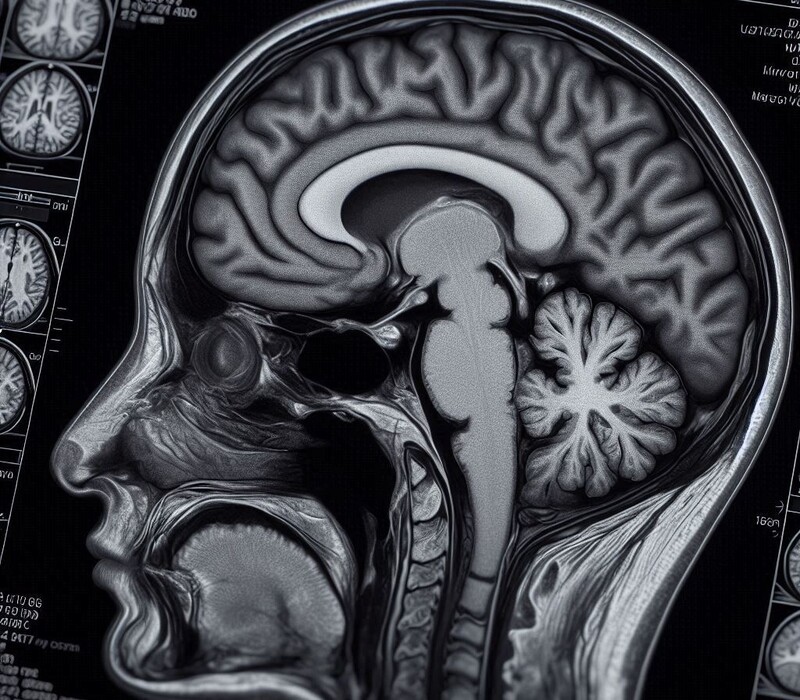

Deux révolutions qui fusionnent. L’imagerie par résonance magnétique (IRM) a été une avancée gigantesque pour la santé, permettant, à la fin du siècle dernier, de voir pour la première fois le cerveau en fonctionnement. Cette technique, qui a valu le prix Nobel de médecine à Peter Mansfield et Paul Lauterbur en 2003, a ouvert une fenêtre vers les secrets de notre organe le plus mystérieux, propulsant les neurosciences dans une nouvelle ère.

Or, une vingtaine d’années après, une nouvelle révolution bouleverse la santé : l’intelligence artificielle. Ce n'était qu'une question de temps pour que ces deux percées technologiques se rejoignent. C’est désormais le cas, grâce à une IA spécialisée conçue par des chercheurs de l’Université du Michigan aux États-Unis. Leur approche, qui automatise la détection de problèmes neurologiques lors des IRM, a été présentée le 6 février 2026 dans la revue Nature Biomedical Engineering.